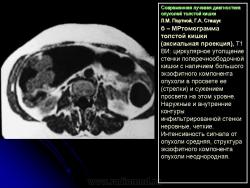

Отображение опухоли толстой кишки на компьютерных томограммах зависит от локализации процесса и характера роста. При преимущественно диффузном внутристеночно растущем раке кишки, что выявлялось гораздо чаще, при КТ отмечалось утолщение стенки кишки с неравномерным, достаточно часто циркулярным сужением просвета соответствующего участка ее, ригидностью стенки (отсутствием изменения диаметра просвета и толщины стенки при дозированном введении воздуха) и неровными внутренними контурами (рис. 11). При экзофитном характере роста опухоли при КТ внутри просвета кишки определялось дополнительное мягкотканное образование с неровными бугристыми контурами, широко прилежащее к стенке кишки. Опухоли были различной структуры: однородной, неоднородной за счет включений кальция или участков распада с наличием в опухолевой ткани жидкости и газа. При появлении газа в околокишечной клетчатке чаще всего предполагалась перфорация ее стенки. Кроме оценки состояния стенок кишки, пораженной опухолью, оцениваются и изменения в окружающих тканях и органах при распространении ее за серозную оболочку. Степень местного распространения опухоли является одним из определяющих факторов прогноза и выбора дальнейшей тактики лечения. Оценку степени распространения опухоли проводили в соответствии с Международной классификацией по системе ТNM.

При КТ слои стенки кишки не визуализируются, в связи с чем разграничить стадии Т1 и Т2 не представляется возможным. Принципиально важно с точки зрения тактики дальнейшего лечения и прогноза заболевания диагностировать прорастание серозной оболочки кишки (Т3) и смежных органов (Т4). Одним из симптомов стадии Т3 является наличие в клетчатке, окружающей кишку, тяжистых или линейных структур, распространяющихся в виде лучей от стенки измененной кишки в жировую ткань или наличия узловой структуры вблизи наружного контура пораженной опухолью стенки кишки (рис. 12).

При этом необходимо четко учитывать топографическую анатомию хода петель кишки, когда косой ход может дать эффект “дополнительного объема”. Во избежание этого желательно проведение исследования с дополнительным введением воздуха в кишку. Кроме того, достаточно трудно разграничить воспалительные изменения и отек в клетчатке, нередко сопутствующие опухоли (рис. 13).

Распространение на смежные органы и висцеральную брюшину (Т4) диагностировалось на основании симптомов “дополнительного узлового объемного образования” по наружному контуру кишки в зоне опухолевого поражения, выраженной инфильтрации клетчатки, брыжейки, отсутствия границ между измененной стенкой кишки и прилежащими органами. На выявление инвазии опухоли в окружающие органы влияет количество жира: чем его меньше, тем труднее диагностика. Очень помогает выявлению распространенности опухолевого процесса на смежные органы и структуры проведение полипозиционного исследования, заполнение прилежащих полых органов (петель тонкой кишки, полости мочевого пузыря) контрастными смесями или газом. Признаками метастазирования опухоли кишки в лимфатические узлы брюшной полости и забрюшинного пространства считались увеличение их диаметра более 15 мм и склонность к слиянию в конгломераты. Однако при высокой чувствительности выявления увеличенных лимфатических узлов по данным КТ (до 95%), специфичность этого метода, как и других – УЗИ, МРТ, остается достаточно низкой (до 33%). В то же время выявление метастазов в печень характеризуется достаточно высокой специфичностью метода (до 99,6%) и чувствительностью (до 73%). Это относится к метастазам, диаметр которых в основном более 10–12 мм. Метастатические очаги в печени меньших размеров (до 5–7 мм) диагностировать значительно сложнее. Как и другие авторы, мы считаем, что КТ не должна применяться в качестве метода первичной диагностики опухоли, но она дает значительный объем дополнительной информации о распространенности опухоли и особенностях ее роста. Особую ценность КТ имеет при выраженных опухолевых стенозах, когда невозможно использовать другие методы диагностики, в том числе и эндоскопию, а иногда и традиционные рентгенологические методики. Поэтому КТ – это один из основных методов повышения точности и полноты диагностической информации, позволяющих диагностировать стадию опухолевого процесса до проведения операции, что определяет выбор схемы лечения и, следовательно, прогноз его результатов.